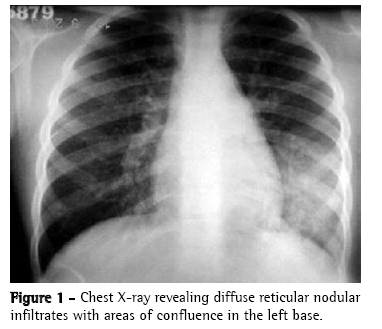

Chest X-ray revealed diffuse reticular nodular infiltrates with areas of confluence on the left base, mimicking acute pneumonia (Figure 1).